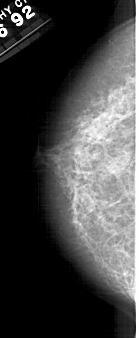

A_1388_1.LEFT_MLO

DATE_OF_STUDY 16 12 1992

PATIENT_AGE 55

DENSITY 4

LEFT_MLO LINES 5281 PIXELS_PER_LINE 2176 BITS_PER_PIXEL 12 RESOLUTION 43.5 NON_OVERLAY